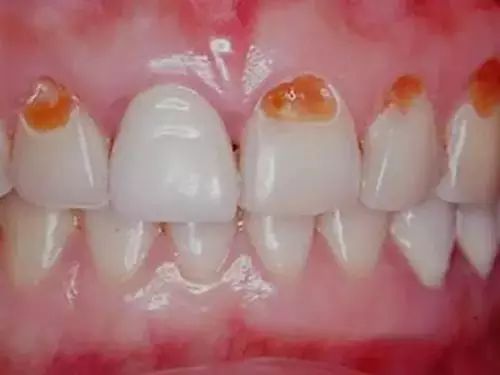

因为,大部分饮料的PH值在2.2 - 4.9之间,而牙齿表面珐琅质的溶解临界PH值是5.5!如果你饮料不离口,就等于是把牙齿泡在这样的液体中,慢慢溶解!

在最极端的状态下,它甚至可以毁掉你的整口牙齿!

如下图

在医学领域,这一现象被称作“酸蚀症”,简单来说就是牙齿长期广泛接触酸性物质造成的牙齿硬组织溶解丧失。